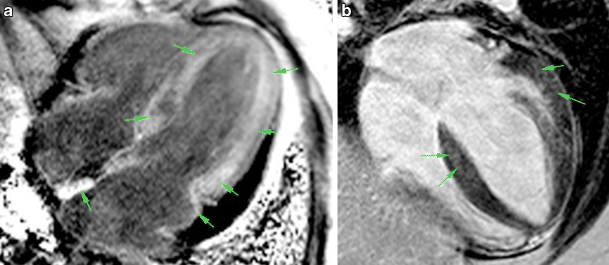

Typical (a) and atypical (b) LGE patterns. Both images are acquired with PSIR sequence in 4‑chamber long axis view. Areas of LGE are indicated by arrows. LGE late gadolinium enhancement, PSIR phase-sensitive inversion recovery